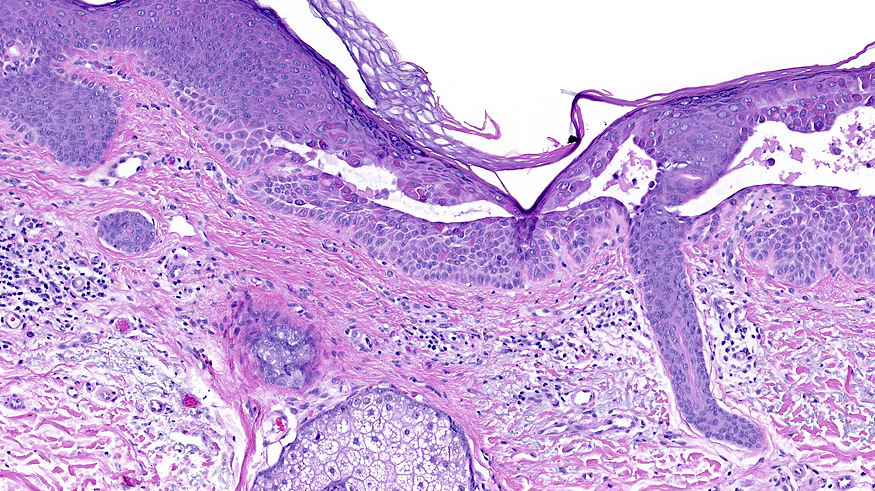

Microscopic (histologic) description

- Suprabasal acantholysis with vesicle formation is the principal microscopic finding

- Elongation of rete ridges with focal acantholysis and eosinophils may be the only early changes in Grover disease

- Main 4 histopathological patterns are:

- Pemphigus vulgaris / foliaceous-like: predominantly limited to suprabasal acantholysis, with basal keratinocytes attached to basement membrane forming a characteristic tombstone appearance

- Darier-like: suprabasal acantholysis of keratinocytes with scattered apoptotic or dyskeratotic cells within various levels of the epidermis

- Spongiotic: edema within epidermis, causing separation of keratinocytes and prominent intracellular bridges

- Hailey-Hailey-like: suprabasal acantholysis of all levels of the epidermis without significant dyskeratosis (dilapidated brick wall appearance)

- More than one pattern can be seen in the same setting

Microscopic (histologic) images